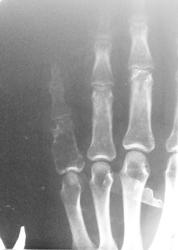

Пол пациента: Женский пол Тип патологии: Травма Область исследования: Скелетно-мышечная система Методы исследования: Rg Мужчина 38 лет, с травмой кисти направлен для исключения перелома........ пардон за качество ) https://radiomed.ru/sites/default/files/styles/case_slider_image/public/user/16833/20121211_095016.jpg?itok=cQfG31Hk ID:25089 Ср, 12/12/2012 - 14:42 #1 Катенёв Валенти... Не на сайте Был на сайте: 7 лет 3 недели назад Зарегистрирован: 22.03.2008 - 22:15 Публикации: 54876 Снимок конечно не фонтан, но предположить можно энхондрому. Ср, 12/12/2012 - 14:46 #2 Mihail63 Не на сайте Был на сайте: 9 лет 9 часов назад Зарегистрирован: 20.11.2012 - 10:31 Публикации: 154 Перелома не вижу +1 за энхондрому проксимальной фаланги 5 пальца Ср, 12/12/2012 - 19:44 #3 И.Бондаренко Не на сайте Был на сайте: 18 часов 48 минут назад Зарегистрирован: 13.09.2011 - 22:55 Публикации: 9206 Патологическмий перелом основной фаланги. Ср, 12/12/2012 - 20:38 #4 Сан Саныч1 Не на сайте Был на сайте: 11 месяцев 3 недели назад Зарегистрирован: 07.06.2010 - 21:17 Публикации: 2114 А что насчет болезни имени простого русского мужика Реклингхаузена? Хочешь сделать что-то нормально - сделай это сам! Ср, 12/12/2012 - 20:58 #5 Наталия Васильевна Не на сайте Был на сайте: 5 лет 9 месяцев назад Зарегистрирован: 25.09.2011 - 09:02 Публикации: 754 Или гигантоклеточная с переломом основания. Ср, 12/12/2012 - 23:03 #6 Special.K Не на сайте Был на сайте: 8 лет 10 месяцев назад Зарегистрирован: 09.08.2012 - 23:08 Публикации: 479 Наталия Васильевна wrote: Или гигантоклеточная с переломом основания. я в заключении написал именно так. перелом проксимального эпифиза основной фаланги и подозрение на новообразование (дифф. диагноз с ГКО). Ср, 12/12/2012 - 23:10 #7 vasyablack Не на сайте Был на сайте: 12 лет 3 недели назад Зарегистрирован: 22.03.2012 - 23:38 Публикации: 53 1.энхондрома 2.киста Чт, 13/12/2012 - 19:15 #8 НБ Не на сайте Был на сайте: 11 лет 5 месяцев назад Зарегистрирован: 07.11.2012 - 19:55 Публикации: 84 Костная киста, патологический перелом. Н.Б. Пт, 14/12/2012 - 17:17 #9 Брысковский Дмитрий Не на сайте Был на сайте: 9 месяцев 2 недели назад Зарегистрирован: 08.11.2011 - 11:00 Публикации: 187 пункция в помощь исследователю) None are more hopelessly enslaved than those who falsely believe they are free

Снимок конечно не фонтан, но предположить можно энхондрому.

Перелома не вижу

+1 за энхондрому проксимальной фаланги 5 пальца

Патологическмий перелом основной фаланги.

Или гигантоклеточная с переломом основания.

я в заключении написал именно так. перелом проксимального эпифиза основной фаланги и подозрение на новообразование (дифф. диагноз с ГКО).

1.энхондрома

2.киста

Костная киста, патологический перелом.